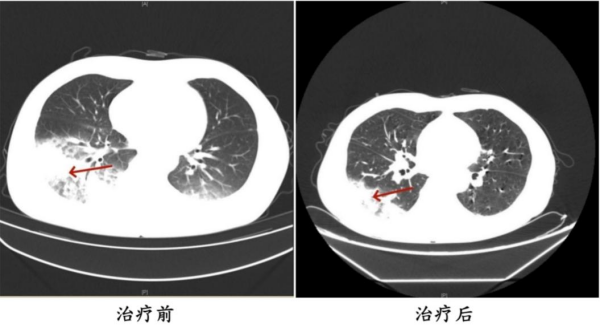

军团菌肺炎CT影像

入院后,呼吸与危重症医学科副主任、副主任医师刘达详细询问患者病史,得知她既往有2型糖尿病、甲状腺恶性肿瘤(乳头状癌术后)、甲状腺功能减退、特纳综合征等病史,是免疫力低下人群。再结合体格检查及相关辅助检查结果,初步判断患者为重症社区获得性肺炎。经抗感染治疗后,患者的病情逐渐加重,反复高热,出现多脏器功能异常,如心肌酶谱异常升高、低钠血症、血尿、蛋白尿等状况。刘达及团队通过分析患者咳出橘红色痰以及肺内、肺外表现,建议完善病原学检查,最终确诊为重症军团菌肺炎。调整用药后,患者病情迅速好转,体温逐渐恢复正常,各项指标逐步恢复。